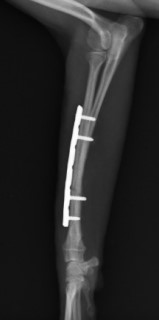

手術後

ロッキングプレートで整復しました。